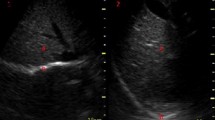

Subcostal approach: excursion

Diaphragmatic excursion is measured with a low frequency phased-array or curved-array (“abdominal”) probe (2–5 MHz) positioned just below the costal arch at the midclavicular line, with the patient in semi-seated position and by angling the ultrasound beam as much as possible cranially and perpendicular to the diaphragmatic dome (Fig. 1). The diaphragm is identified as a bright line covering the liver and the spleen. Obtaining a clear image of the left hemidiaphragm can be difficult due to the poor acoustic window of the spleen. During inspiration, the diaphragm should move toward the probe (Fig. 1). Excursion is quantified in M-mode, with the M-line placed perpendicular to the direction of motion (Fig. 1); the sweep speed is best adjusted to around 10 mm/s to obtain a minimum of three respiratory cycles within one image. Diaphragm excursion should only be measured during unassisted breathing (i.e., T-piece or minimum tolerable CPAP level), since active contraction of the diaphragm cannot be distinguished from passive displacement due to ventilator inspiratory pressures [4, 12].

In a cooperative patient, a maximum inspiratory effort is performed to assess maximal excursion. Excursion of both hemidiaphragms is compared to identify unilateral weakness or paralysis (for reference values, see Table 1). The success rate for visualizing excursion is high during tidal breathing (> 95%), whereas during maximal breathing visualization is more difficult, especially on the left side [17].

If experiencing difficulties visualizing the diaphragm from the subcostal window, movement of the liver or spleen during tidal respiration can be used as an alternative. To this end, an intercostal window at the zone of apposition in B- or M-mode is advised, using a low frequency probe [18, 19]. As there is some inconsistency in agreement between diaphragmatic- and subdiaphragmatic excursion [20, 21], it is advised to use this approach for a qualitative rather than a quantitative assessment of diaphragm motion.